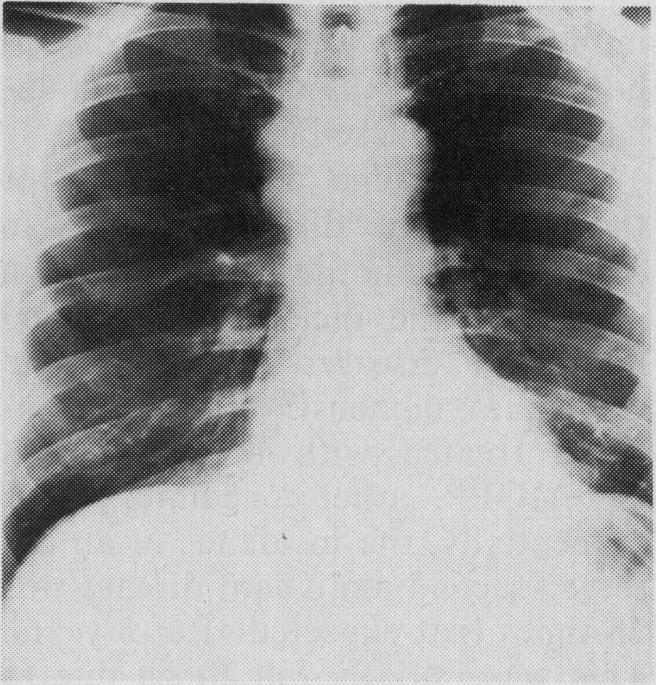

We describe a patient in whom lung cancer developed several years after he had received combined-modality therapy for Hodgkin's disease. The literature concerning second malignant diseases, particularly thoracic tumours, that occur following combined-modality therapy for cancer is reviewed. It is important to recognize these entities, because chest symptoms or findings on x-ray films may be misinterpreted as representing late recrudescence of the first neoplastic disease.

我们描述了一名患者,他在接受霍奇金病联合治疗数年后患上了肺癌。本文回顾了有关癌症联合治疗后发生的第二原发性恶性疾病,尤其是胸部肿瘤的文献。认识到这些疾病很重要,因为胸部症状或X线片上的表现可能会被误解为代表第一种肿瘤疾病的晚期复发。